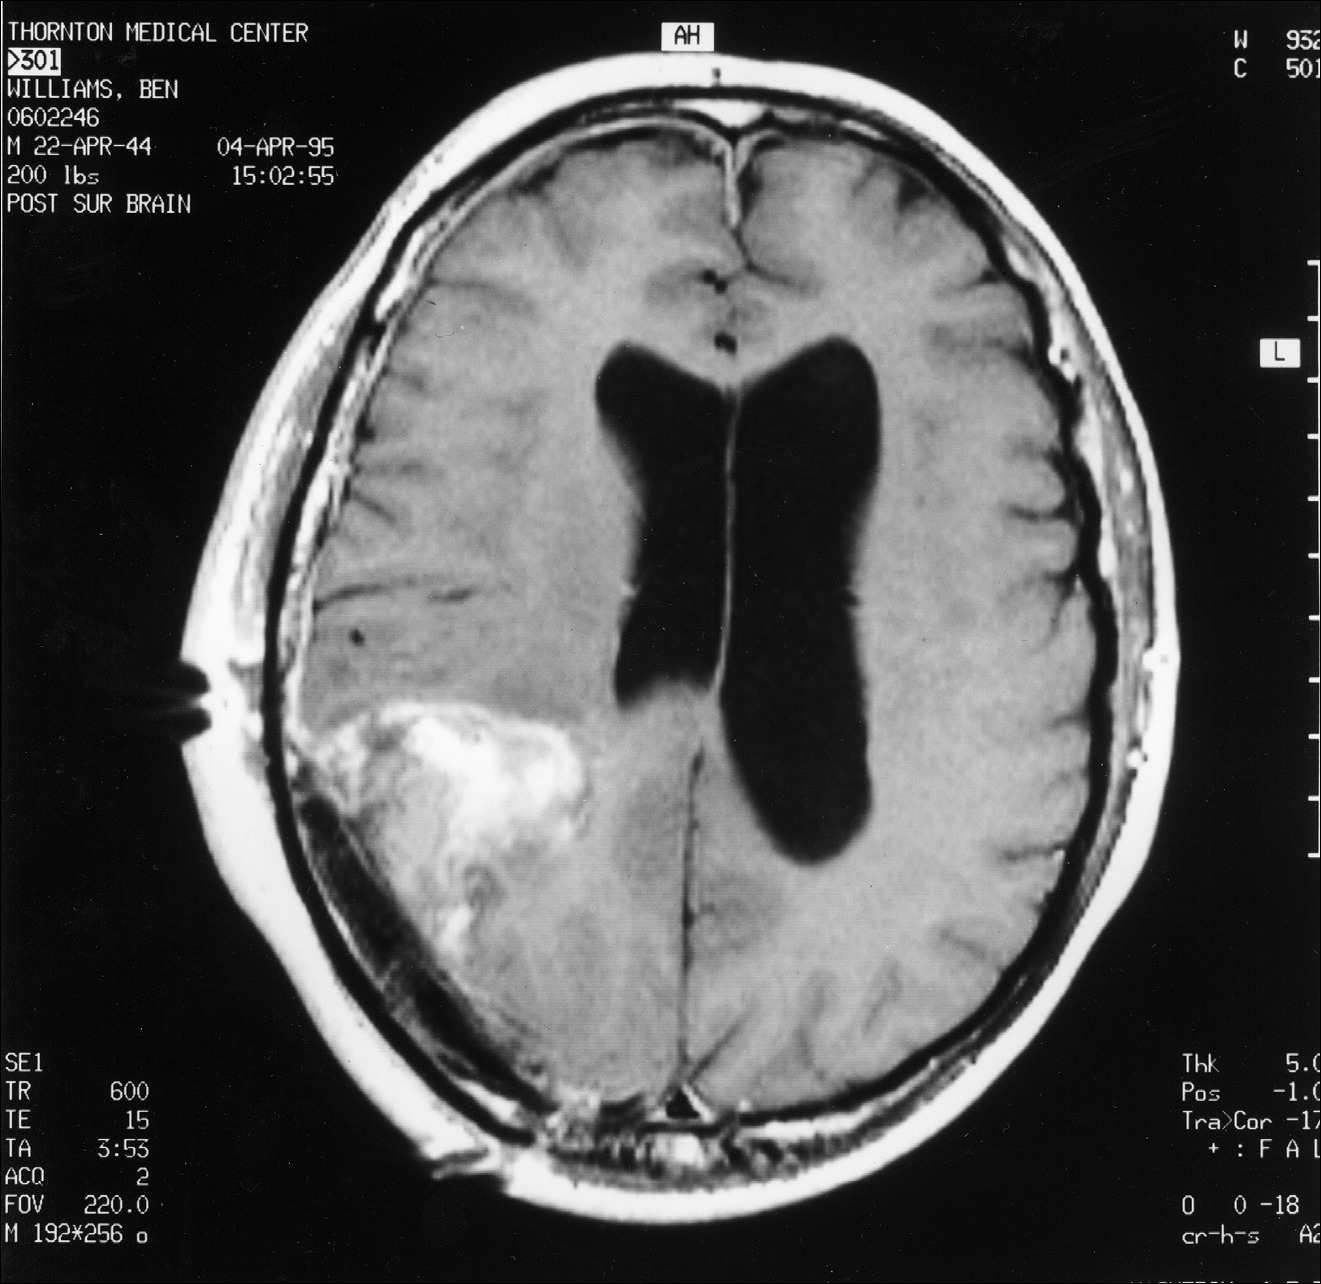

Kitą rytą su Diane susitikome su dr. Marshall aptarti MRT rezultatų. Jis paaiškino, kad stengėsi pašalinti visą matomą naviką, tačiau toli už jo ribų nėjo. Navikas buvo toks didelis, kad papildomas šalinimas būtų sukėlęs rimtų mano regėjimo problemų. Gliomos tipo smegenų navikai turi mikroskopinius ūselius, besitęsiančius du–tris centimetrus už matomų naviko ribų, todėl pašalinti visas naviko ląsteles yra nepaprastai sunku. Tik patys agresyviausi neurochirurgai sugeba pašalinti šiuos nematomus ūselius, dažnai sukeldami reikšmingą paciento funkcinį pablogėjimą. Kadangi dr. Marshall operavo konservatyviau, mano MRT parodė, kad liko nemaža naviko dalis (žr. čia ir čia). Dr. Marshall neatrodė ypač susirūpinęs dėl likusio naviko ir paminėjo, kad jo kolega dr. David Barba galėtų jį veiksmingai gydyti spindulinės terapijos implantu, vadinamu brachiterapija. Tuo metu neturėjau supratimo, apie ką jis kalba. Mano mintis užvaldė tai, kad po operacijos liko nemaža naviko dalis.

4 pav.

Pooperacinis MRT pjūvis, atliktas per smegenų vidurį tarp viršaus ir apačios. Abu pjūviai rodo, kad po operacijos liko nemaža naviko dalis.